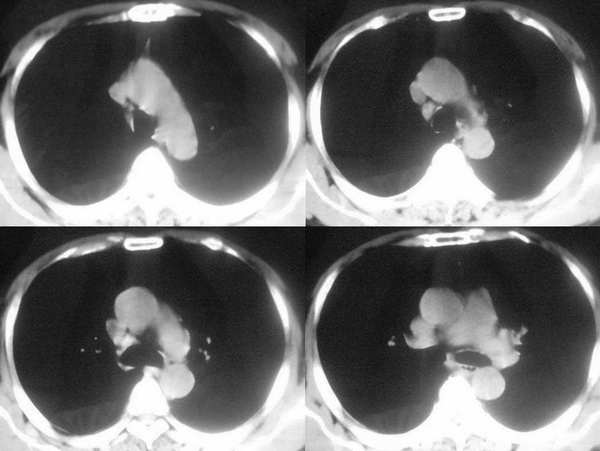

右肺下叶基底段团块状病灶,其内见偏心性空洞,洞内未见液平面,可见壁结节;双肺野及双侧胸膜见多发大小不等软组织密度结节影,边缘较光滑,部分肺内结节有空洞形成;纵隔内见有重大淋巴结;右侧见少量胸腔积液。

双肺胸膜下见大小不等圆形类圆形结节影,边缘较光滑;右肺下叶基底段靠隔顶及纵隔旁见团块状病灶,其内见偏心性厚壁空洞,洞内见短液平面,壁厚薄不均。纵隔淋巴结增大;右侧见少量胸腔积液。

两肺外周胸膜下可见多发大小不等的结节影,边缘稍模糊,可见细长毛刺,右肺下叶病灶部分融合成片团状,内出现多房空洞,部分内有小液平面,内壁较光整,壁厚不规则。气管前腔静脉后淋巴结肿大。考虑1韦格氏肉芽肿。2真菌感染(隐球菌)。其他待排。

气管前、腔静脉后可见肿大的淋巴结。韦氏肉芽肿为少见病例,发病率远低于肺癌